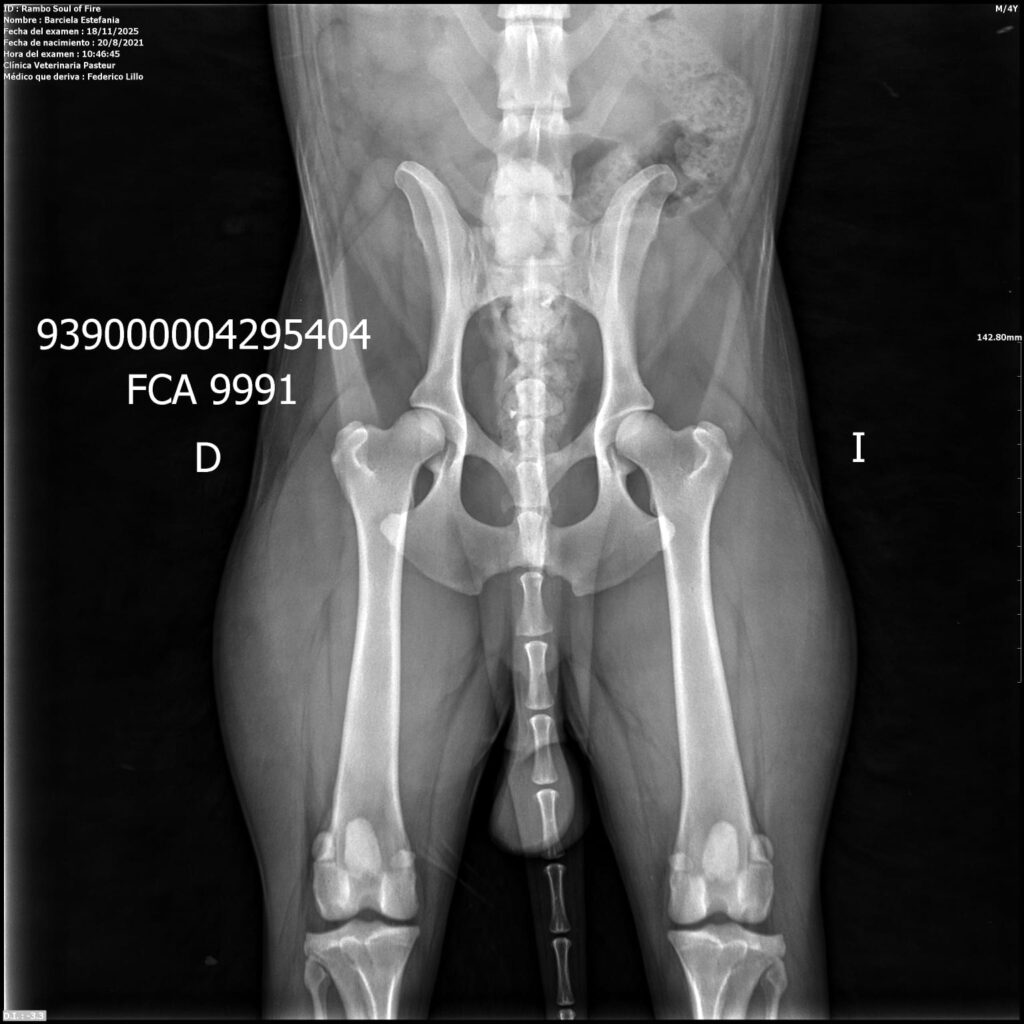

Placas de caderas y codos en La Rienda Border Collie

En La Rienda Border Collie la cría responsable no es un eslogan: es una forma de trabajar desde hace años. Por eso, nuestros machos reproductores y algunas de nuestras hembras cuentan con estudios radiológicos de caderas y codos, un paso clave para garantizar cachorros sanos, equilibrados y con una excelente calidad de vida.

Realizamos radiografías oficiales de caderas y codos a nuestros reproductores, evaluadas por profesionales veterinarios especializados.

Estos estudios permiten detectar posibles patologías hereditarias, como la displasia de cadera y de codo, ayudando a reducir su incidencia generación tras generación.

✔ Clasificación A en caderas y codos, indicativo de articulaciones sanas y excelente conformación

✔ Clasificación A en codos y B en caderas, siempre informada con total transparencia y criterio de selección responsable